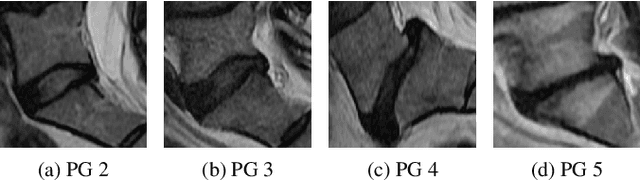

Abstract:This paper addresses the challenge of grading visual features in lumbar spine MRI using Deep Learning. Such a method is essential for the automatic quantification of structural changes in the spine, which is valuable for understanding low back pain. Multiple recent studies investigated different architecture designs, and the most recent success has been attributed to the use of transformer architectures. In this work, we argue that with a well-tuned three-stage pipeline comprising semantic segmentation, localization, and classification, convolutional networks outperform the state-of-the-art approaches. We conducted an ablation study of the existing methods in a population cohort, and report performance generalization across various subgroups. Our code is publicly available to advance research on disc degeneration and low back pain.